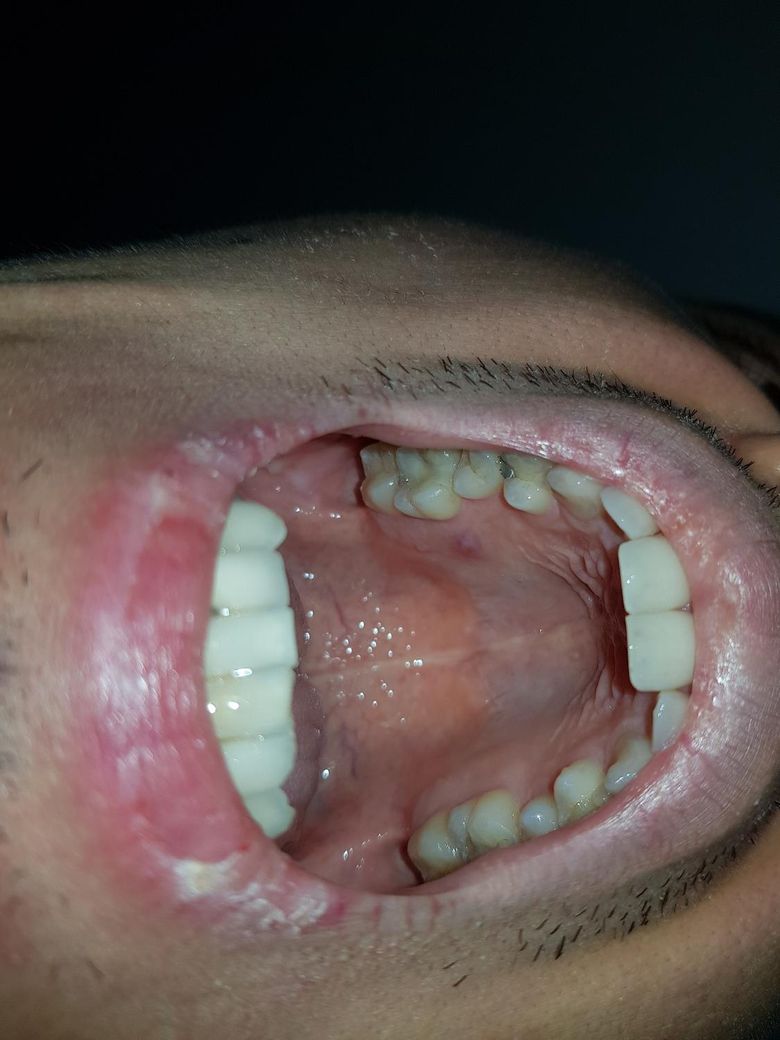

3월 7일의 사진인데 3월 6일에 불편감때문에 저녁양치후 포크로 뜨거운물 에탄올소독후 살짝찔렀습니다

속이나 겉이나 저 부분만 물렁하고 포크날중 한개만 쉽게 닿을수 있었습니다

나온게 점액질이 조금 있어보이고 미세하게 누렇고 희미한 액체였습니다

터뜨리면 바로 다나올줄알았는데 자기전까지 천천히 작아지더라고요

20일 사진입니다 아예 없어진 느낌이 며칠지나고 19일에 약간 다시 입천장에 이물있는 느낌만들다가

작은뾰루지가 20일식사후 하나 올라왔습니다 그래서 아침식사후 치약없이 양치한뒤 다시터트렸고

저번에 천천히나왔던거때문에 석션기로 카테터없이 범위를 넓게해서 피랑 내부 빨아들였습니다

관소독후 뎄다가 뗐다가 하면서 했더니 금방 이물감 없어졌습니다